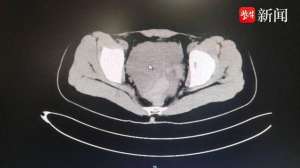

美女啪啪出血(女孩同房后大出血,这个病要了解,能救命)10月20日,镇江江大附院(又名江滨医院)介绍,近日20岁的瑶瑶(化名)和男友同房后,突然腹痛难忍,送至江大附院后被诊断为黄体破裂!盆腹腔内积血达800多毫升,幸亏手术及时,才没有酿成大...[详细]